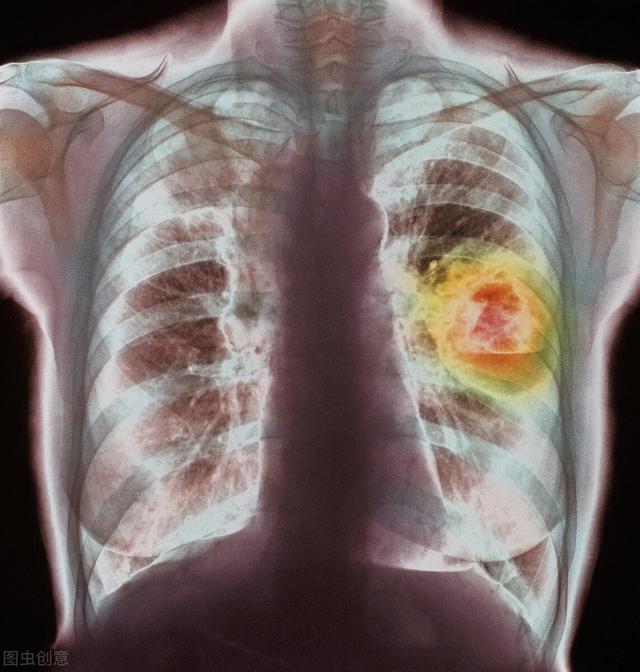

肩や背中の痛み:実は肺がんが原因だった

60歳を超えた孫さん、体はいつも「健康」で、酒とタバコに溺れていた。昨年秋から、時々体調が悪くなる。右肩と背中の関節の腫れ、しびれ、痛み。痛みはこの2ヶ月で悪化し、地域の保健センターで治療を受けている。

医師からは「五十肩」と言われたが、消炎鎮痛剤の内服、鍼治療、マッサージなどを1カ月以上続けても効果はなく、痛みは日に日に悪化している。

地方病院への紹介。胸部CTで右肺尖部にピンポン玉大の影が見つかり、右肺上方腫瘍(肺癌関節症)と診断された。すぐに入院した。

肺がん関節症の症状にはどのようなものがありますか?

高齢者の肩や背中の関節の痛みは、通常、五十肩、関節リウマチ、外傷、その他の病気の結果として見られます。抗炎症薬、抗リウマチ薬、血液うっ滞活性化薬による治療その後、すぐにヒーリング効果を発揮する。

肺がんに起因する肺外疾患肺がん関節症では上記のような効果的でない、あるいは効果のない治療この2つの中で最もわかりやすい特徴である。

肺癌の肺外関節症は、その臨床症状において五十肩や関節リウマチなどの変形性関節症と類似している。高齢者における関節症を合併した肺癌の発生率は約10〜20%であると報告されている。

そのような患者のうちほとんどの症例は、初期段階では特異的な徴候がなく、咳や発熱はなく、背中や関節の痛みだけである。患者に無視されたり、他の病気と誤診されたりしやすく、患者が有利な治療を受ける良い機会を失ってしまう。

エビデンスに基づく医療では、以下のことが判明している。肺癌関節症の症状は、肺の徴候に数ヶ月以上先行する。病状は急速に進行し、通常の抗炎症薬や鎮痛薬は効かない。